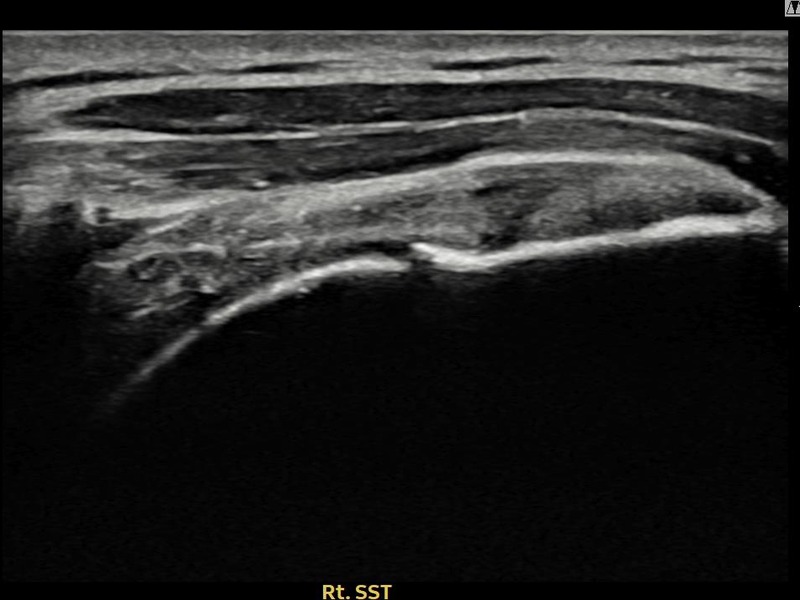

김ㅇㅇ님 · 우측 극상근건 점액낭면측 부분파열

우측 어깨 통증으로 팔을 들어올리기 어렵고 취침 시 통증이 심해 내원하셨습니다. 점액낭면측 부분파열에 대해 축소봉합술을 시행하였고 힘줄 구조가 완전히 회복되었습니다.

상세 보기 →